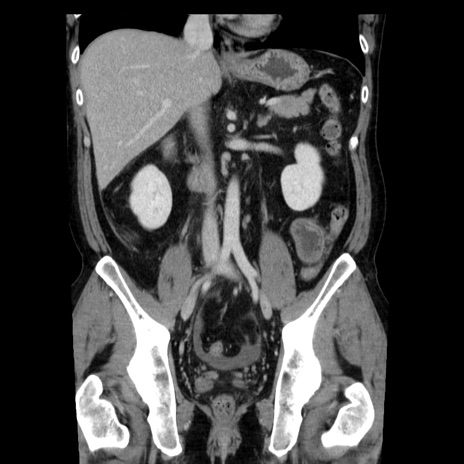

症例29(冠状断像)

【症例】40歳代男性

【現病歴】2日前から胃痛あり。徐々に周期的な激痛に変化した。本日になっても激痛があるため受診。

【身体所見】意識清明、BT 38-39℃台あり、腹部:膨満、やや硬、右下腹部に圧痛あり。

【データ】WBC 8500、CRP 23.26